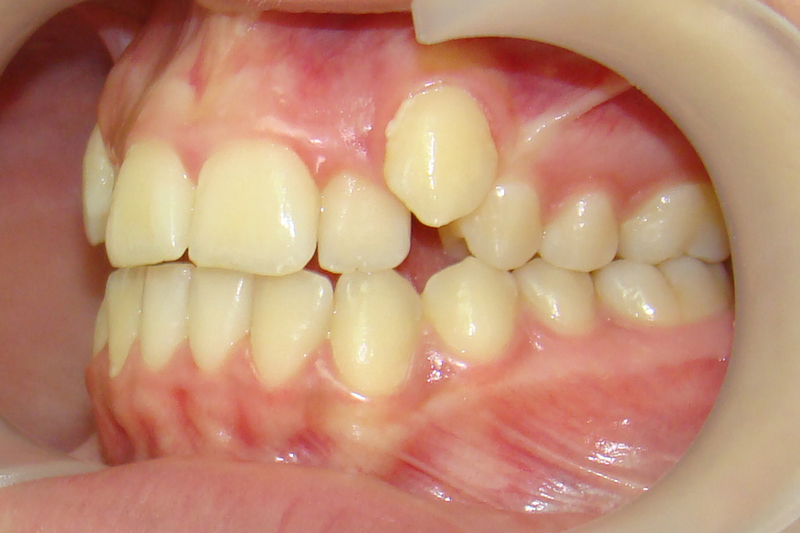

Девушке 14 лет. Получилось все исправить без удаления зубов

А это уже молодой человек 10 лет. Тоже получилось справиться без удаления. Хоть оно и было показано. Но мальчик очень упорно носил специальные аппаратики и резиночки. Покажу со всех сторон. Этот случай победил в конкурсе на конференции